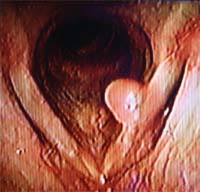

68歳男性。のどが痛い 喫煙暦 40本x50年 右声帯、仮声帯に腫瘍 |